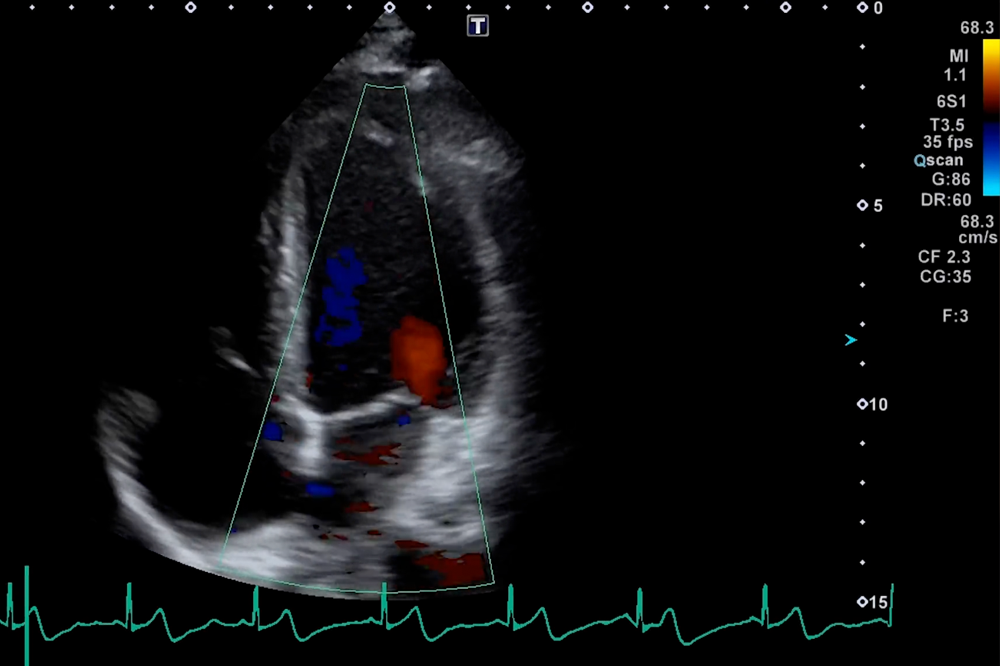

支持甲状腺,乳腺,心脏,腹部,盆腔等多部位高清检查。乳腺检查中融合AI影像分析技术,可实时提供诊断辅助支持。